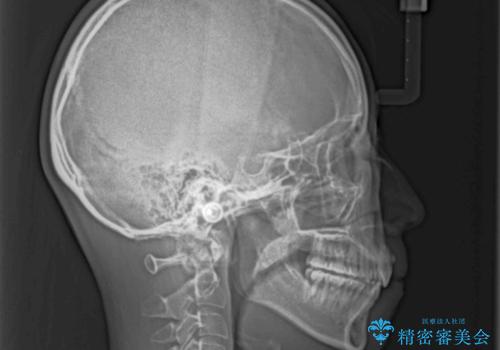

4本の歯を抜歯したことで、飛び出していた口元が引っ込み、横顔が大きく改善されました。

咬み合わせが悪化することのないようにスペースを閉じていくことができ、比較的スムーズに治療を進めることができました。